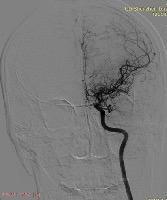

因脑血管造影中脑底异常血管网形似烟雾,故称之为烟雾病。通俗地说,就是交通主干道发生了堵塞,为了疏通车辆,主干旁边的羊肠小道都开放了,分流车辆。在这里,主干道就是颈内动脉、大脑中动脉和前动脉;而羊肠小道就是烟雾状血管。这样“变形”的好处是尽量保证大脑不缺血缺氧。

二、为什么会得烟雾病,关于本病病因,目前国际上尚无定论,一般认为与以下因素有关:①遗传因素。家族性烟雾病大概占所有病例的12%,也就是说,有超过十分之一的烟雾病患者其家庭成员也同样患有此病。所以在确诊烟雾病后,家人一定要注意排查。②免疫炎症因素。目前研究发现,有许多参与免疫炎症反应的细胞因子和负症因子在该病中出现异常。总之,一般认为该病的发生是多种因素共同作用的结果。烟雾病血管造影表现为颈内动的来福闭塞,烟雾状血管形成

四、烟雾病的诊断,根据患者年龄、性别及临床表现可初步疑诊烟雾病,烟雾病的确诊需要进行影像学检查,包括MRI和DSA.由于脑血管造影为有创性检查,对于儿童来讲,一般MRI即可诊断,不过对于需要手术的儿童,也需要进行DSA诊断。脑血管疾病烟雾病的诊断标准:①起始段狭窄或闭塞。②脑血管造影出现颅底异常血管网,行头部MRI时,在界答组等状血管两。③上述影像学特征呈双侧。需要排除引起烟雾病的一些常见疾病。